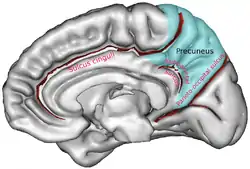

Sagittal MRI slice with the precuneus shown in red. (Anterior to the left.) | |

In neuroanatomy, the precuneus is the portion of the superior parietal lobule on the medial surface of each brain hemisphere. It is located in front of the cuneus (the upper portion of the occipital lobe). The precuneus is bounded in front by the marginal branch of the cingulate sulcus, at the rear by the parieto-occipital sulcus, and underneath by the subparietal sulcus. It is involved with episodic memory, visuospatial processing, reflections upon self, and aspects of consciousness.

The precuneus is located on the inside between the two cerebral hemispheres in the rear region between the somatosensory cortex and forward of the cuneus (which contains the visual cortex). It is above the posterior cingulate. Following Korbinian Brodmann it has traditionally been considered a homogeneous structure and with limited distinction between it and the neighboring posterior cingulate area. Brodmann mapped it as the medial continuation of lateral parietal area 7.

Precuneus of left cerebral hemisphere (shown in red).

Precuneus of left cerebral hemisphere (shown in red). Medial surface of left cerebral hemisphere. (Precuneus visible at top left.)

Medial surface of left cerebral hemisphere. (Precuneus visible at top left.) Medial surface of left cerebral hemisphere. (Precuneus colored in red.)